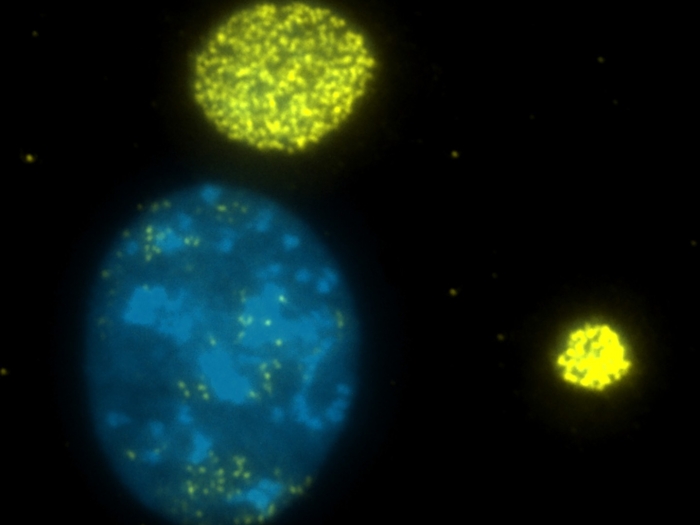

cancer cell yellow blue

Health Lab

Research sheds light on low rates of genetic testing for cancer

Research finds genetic testing for cancer can bring more knowledge to patients and their relatives, but not many people get it done.